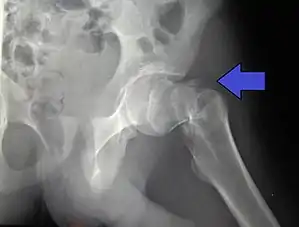

A hip fracture is a break that occurs in the upper part of the femur (thigh bone), at the femoral neck or (rarely) the femoral head.[2] Symptoms may include pain around the hip, particularly with movement, and shortening of the leg.[2] Usually the person cannot walk.[3]

| Intertrochanteric hip fracture in a 17-year-old male | |